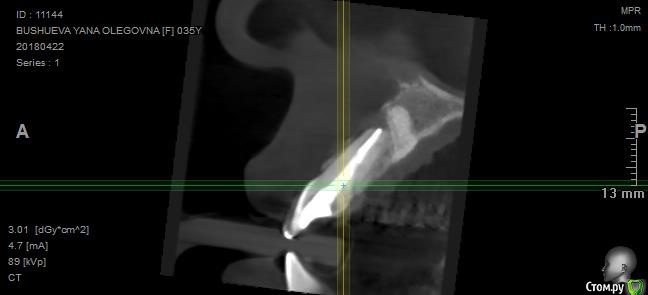

Vilka Опубликовано 17 мая, 2018 Поделиться Опубликовано 17 мая, 2018 Добрый день уважаемые специалисты. Моя история: http://forum.stom.ru/topic/30641-rezektciia-21-zuba/http://forum.stom.ru/topic/31532-oslozhneniia-posle-rezektcii-izlishki-kostnogo-ma/ Если кратко: у меня опять рецидив кисты на единичке слева. На десне образовалось уплотнение, терапевт, сделав снимок, сказала, что это свищ, но кисту не видит. Отправили на КТ, посмотрев его хирург, который проводил резекцию, сказал, что киста сбоку корня (но где именно не знаю, так как с этим врачом мне пока пересечься не удалось). Вердикт: зуб удалять. Ну или опять резекция. В другой клинике кисту сбоку не видят, видят ее сверху, где темное пятно. В этой клинике зуб также советуют удалять. Врач, который проводил резекцию ранее мне объяснял, что темное пятно КТ это пустота, которая образовалась из-за удаления излишков биоса - на предыдущих кт это пятно уже было. Вопрос: удалять в любом случае? Срез смогла сделать только такой.Ссылка на КТ https://ru.files.fm/u/7zzyga5n Заранее всем спасибо. Ссылка на комментарий